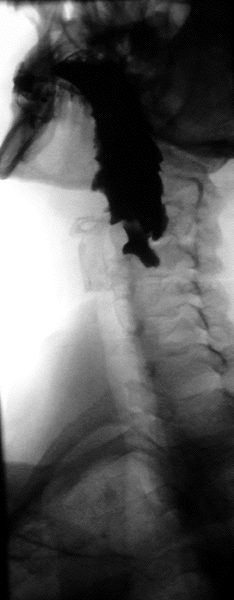

En anatomie, un diverticule de Zenker est un diverticule (une poche) de pulsion qui se forme au-dessus du sphincter œsophagien supérieur entre le faisceau thyroïdien du muscle constricteur inférieur et le faisceau cricoïdien du muscle constricteur inférieur (aussi appelé muscle cricopharyngien).

Le diagnostic est radiologique. Aujourd'hui l'imagerie de première intention à effectuer est un scanner cervico-thoraco-abdomino-pelvien avec opacification digestive haute ainsi qu'injection de produit de contraste. Le transit œso-gastro-duodénal historiquement utilisé qui visualise le diverticule sous forme d'une image d'addition du tiers supérieur de l'œsophage n'a pratiquement plus d'indication à l'heure actuelle en raison de la meilleure précision de l'examen TDM[1].